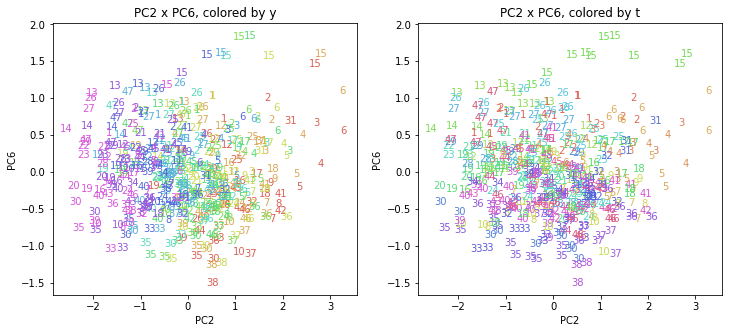

PCAの結果の第n主成分をPCnと表記します。

医療費データの場合と同様に、PCAの結果を見やすく表示するため、seabornのカラーパレットを使って、年月別、都道府県別に色分けして図示してみます(左側が年月別に色分け、右側が都道府県別に色分け)。PC1~PC8まで表示しました。

都道府県番号の表示

上の色分けだけでは都道府県が区別しにくいので、医療費データの場合と同様に、点の代わりに都道府県番号をプロットした図も描いておきます(色分けは上と同じ)。

医療費データの場合ほどはっきりとはしていませんが、PC2が概ね時間の経過を表す成分で、残りの成分が時点によって変わらない地域の特徴を表す成分となっているようです。

また、PC1×PC3を見ると、47沖縄が他の都道府県からかなり離れたところに位置しており、沖縄の地域差が際立っているのが分かります。これは、以前別の記事で年齢階級のない健診データでPCAを実行した場合と似た結果となっています。

今回は、医療費データと同様に、健診データ240次元についてPCAを実行してみました。PCAの結果、医療費データの場合ほどはっきりしとはしていませんが、第2主成分が概ね時間の経過を表す成分で、時間軸に沿った全体的な動き(全国的な動き)を表しており、それ以外の成分が地域の特徴を表す成分で、この10年間あまり変わっていないことがわかりました。